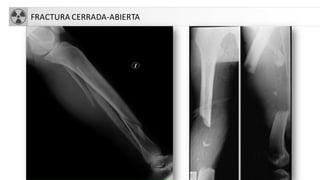

• Cerrada-abierta

FRACTURA CERRADA-ABIERTA